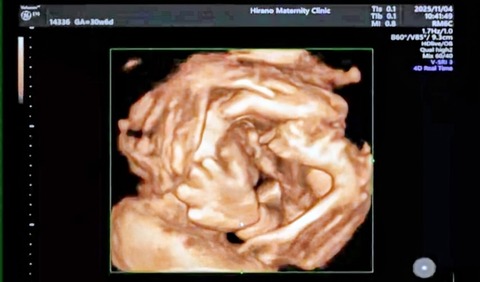

今日は長女の検診日。

10時半予約の産科へ。

前回、お腹の赤ちゃんがそっぽ向いていて、4Dが撮れなかったので

今回撮れました。

目と鼻がわかります

こっちは、ハローって手を出してる様にも。

相変わらず長女は、ケンタッキーフライドチキンにしか見えないと言う(笑)